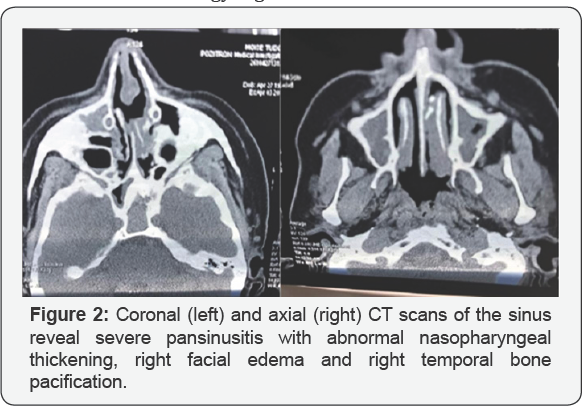

Extranodal NKTCL outside the lymph nodes manifests in the nasal cavity. Patients with this type tend to have earlier disease (stage I) and is associated with Epstein-Barr virus (EBV), irrespective of the ethnicity of the patient, but the exact mechanism of malignant transformation via EBV is not clear till now. Extranodal nasal type NKTCL demonstrates a predilection for the nasopharynx, palate, skin, soft tissues, orbit, gastrointestinal (GI) tract, and testes. Secondary lymph nodes may be involved in some cases; a disseminated leukemia is even possible. Lymphomas that manifest outside of the nose have a strong association with EBV in Asian patients, but not in whites. The pattern of involvement of the extranasal sites has been hypothesized to be related to the marker CD56-neural cell adhesion molecule. The skin is the most common site of dissemination in Etiology Figure 2.

In the same time I order cultures for fungi like Aspergillus, Candidiasis, Mucor. Also I run a battery of blood test to appreciate the general status of the patient others for the differential diagnosis, in fact in that time it was an excluding diagnosis with. Wegener granulomatosis=PANCA, CANCA, biopsy histopathology, IHC Tuberculosis-RX thorax, ex BK direct, cultures, Protein chain reaction, Quanti FERON test Tertiary syphilis guma RBW, VDRL , biopsy histopathology, IHC Leprosy biopsy,B. Hansae, cultures Rhinoscleroma Klebsiella rhinos cleromatis, biopsy histopathology ,IHC Cancers biopsy histopathology, IHC Mucormicosis cultures, biopsy histopathology, IHCCT, MRI scans axial, coronal view revealed pansinusitis, necrosis of the intersinuso nasal wall destruction of the inf turbinate perforation of the nasal septum, the extension of the process also endocranial extension. Finally we send the patient on TG .MURES on Oncological Clinic , where my diagnosis was confirm They report the case and it was the single patient with Lethal Midline Granuloma in Europe. They use an aggressive protocol of chemo-radiotherapy but without response .He return without the nasal pyramid, with the hole in his mid face, with high fever, fetid nasal discharge [21-25].